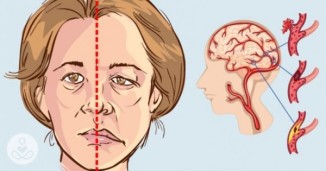

რა აუცილებელი ზომები უნდა მივიღოთ ინსულტის დროს ექიმის მოსვლამდე.

ინსულტი- ( აპოპლექსური შეტევა ) - ტვინში სისხლის მიმოქცევის მკვეთრი დარღვევა, ტვინის ქსოვილების დაზიანება და მისი ფუნქციის მოშლაა. დაავდება სწრაფად..